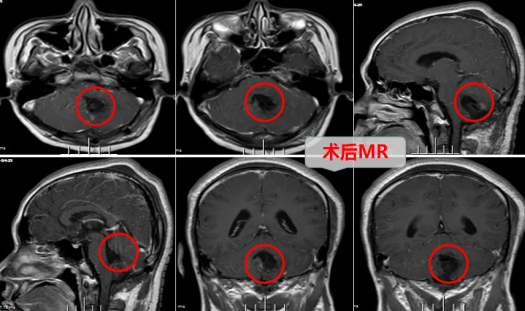

于是姚先生找到当地医院行头颅MRI检查:结果显示:小脑蚓部、四脑室占位,原来是脑子里面长肿瘤了!而且肿瘤竟有33×42×36mm的大小——比鸡蛋还要大!由于肿瘤靠近脑干,手术风险较大,当地医生便介绍姚先生及其家人到省城广州来找有丰富神经外科经验的欧阳辉教授。姚先生随家人来到广州,找到广东三九脑科医院,欧阳教授热情接待了他,并收治到业务能力强的神经外十科。

入院后,外十科团队为姚先生进行了更为详细的检查,姚先生被诊断为:小脑蚓部-第四脑室肿瘤,血管母细胞可能性大。肿瘤虽然囊实性,但此例实性部分占几乎一半,且贴近脑干,CTA检查:显示肿瘤实性部分的血供非常丰富,主要由左侧小脑后下动脉供血,故手术确实有一定的难度和风险。

在完善的检查与充分的术前准备后,家属与姚先生同意由欧阳主任主刀为其于全麻下行肿瘤的切除手术。由于肿瘤实性部分体积较大,而且血管丰富,又贴近脑干,手术非常危险。但是欧阳主任“剑胆琴心”,在智能高清显微镜下,沉着冷静地操作,“抽丝剥茧”,终于将肿瘤完整摘除。术后的姚先生状态良好,康复很快,手术后第十天,就高兴地出院,精神抖擞地回到了汕头。